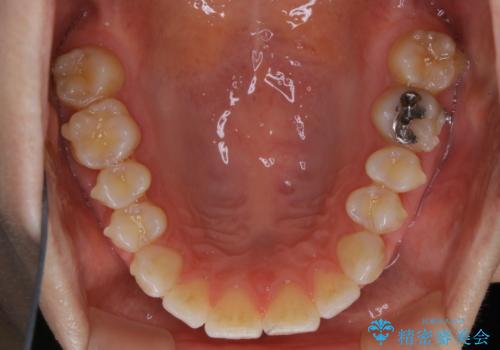

- インビザライン矯正治療中にステインが気になるとのことで来院されました。全体的にステインが付着していたため自費クリーニングPMTC(60分コース)を行いました。

インビザライン矯正治療中は、ご自身の歯にアタッチメントという突起物(効率的に歯の移動を行うため)をつけます。そのため、通常時よりもステインが付きやすい状態になることがあります。

矯正治療中の虫歯・歯周病・口臭予防としても、定期的にPMTCを行うことが大切です。